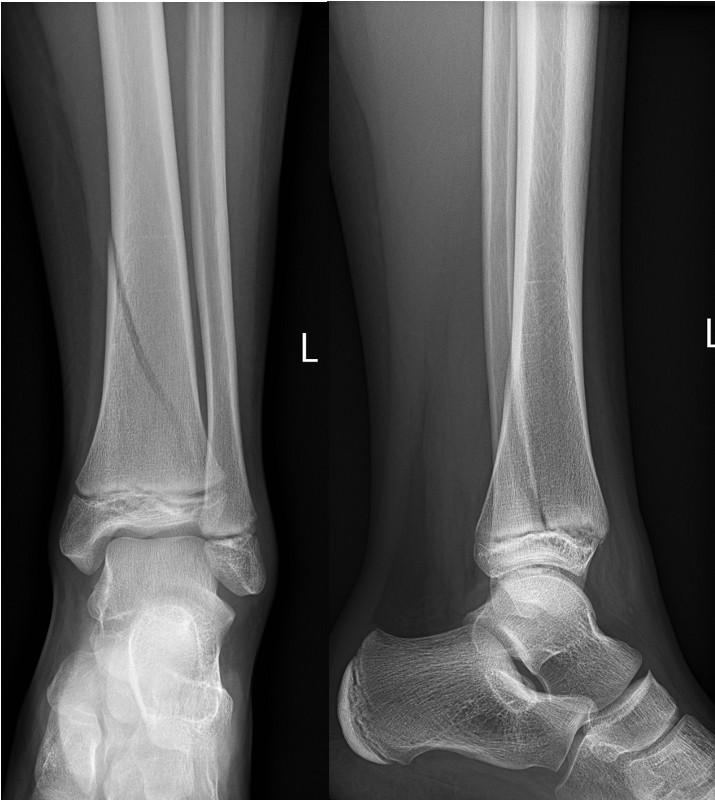

Minimally displaced Salter-Harris II fracture of distal fibula